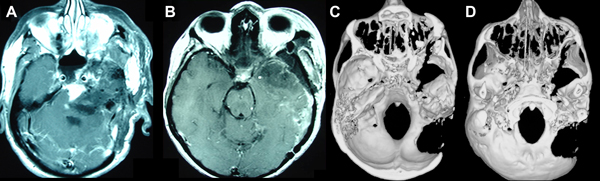

Figura 5. A) y B) RMN con gadolinio, T1, axial, realizada en el post operatorio inmediato. Se observa la exéresis tumoral, huellas quirúrgicas, restos de sangre y materiales hemostáticos. C) Tomografía axial con reconstrucción 3D. Vista de endocráneo. D) Tomografía axial con reconstrucción 3D. Vista de exocráneo. En ambas figuras se aprecia la extensión de la remoción ósea de las cirugías previas y del procedimiento combinado actual: abordajes infratemporal – petrosectomía anterior.